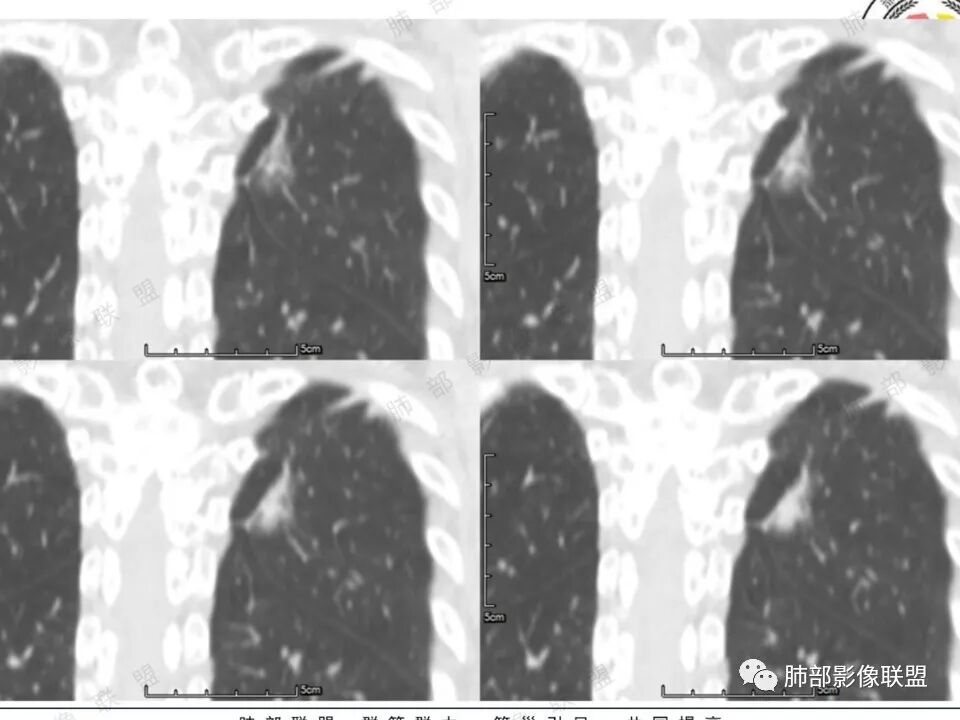

高强化,实性结节,边缘有磨玻璃,有膨隆,斜裂侧偏平直胸膜凹陷,IAC,鉴别炎性肉芽肿

左肺上叶长条状病灶,胸膜牵拉,边缘平直,磨玻璃边界清楚,不均匀强化,考虑炎性,不完全排除肺癌

左肺结节,形态不规则,边缘略收缩,分叶,部分边缘平直,周围可见清晰磨玻璃影,增强后明显强化,考虑:血管瘤,炎性假瘤,鉴别腺癌

左肺上叶尖后段病灶,毛玻璃边界不清,实性成分边缘平直,重建,病灶长条形,增强明显强化,考虑炎症

中年女性,左肺上叶长条状病灶,宽基底与胸膜交界,胸膜凹陷,病灶边缘平直,局部收缩及膨隆,周围可见磨玻璃,其边界清楚,增强病灶不均匀强化,影像表现有炎性病变,也有明显占位表现,考虑OP,有膨胀性表现的小结节,不完全排除肺癌!需要结合相关检查。

体检发现左肺上叶尖后段混合磨玻璃结节,考虑浸润性腺癌可能性大,建议抗感染后复查,明显强化有不支持的地方,左肺上叶尖后段外侧胸膜下小磨玻璃结节,提示AAH。

女,41岁,体检发现肺部结节。左肺上叶长形病灶,具有轻度膨胧感,刀切尖角征,胸膜粘连,早期强化见薄环强化征象,后期有延迟强化特点。病灶周围不是很干净。考虑结核肉芽肿或炎症肉芽肿。

中年女性,查体发现左上肺条块结节,靠近斜裂,边缘平直有收缩,胸膜牵拉,明显强化,考虑炎性假瘤或炎性肉芽肿,鉴别腺癌。

中年女性,体检发现。左肺上叶后段不规则结节灶,密度不均匀,病灶周围可以边界似清非清毛玻璃影,临近胸膜牵拉,增强扫描病灶明显不均匀强化。考虑炎性假瘤,鉴别腺癌。

患者中年女性,体检发现。胸部CT:左肺上叶后段长条形结节灶,边缘光滑,边界清楚,见分叶、毛刺、胸膜牵拉及平直征象。增强明显强化,内可见血管增粗,综合考虑恶性病变,浸润性腺癌可能大,鉴别结核。

41岁女性,左肺上叶不规则结节,边缘见似清非清的磨玻璃影,叶间裂牵拉。整体病灶边缘平直,强化明显。另左上叶外侧尚有一磨玻璃结节(蘑菇兄弟?),考虑炎性肉芽肿可能性大。强化太明显让人很纠结,会不会存在CD,但边缘又有磨玻璃影;腺癌、结核、隐球都没有见过强化这么明显的,强化程度与主动脉基本一致,不会是动静脉畸形吧。

左上肺前后段不规则实性病灶,浅分叶,边缘部分平直收缩,轻微胸膜牵拉,伴周围磨玻璃样改变,强化明显,感觉是炎性恶性征像均有。

左肺上叶后段条片状影,边缘部分模糊,前缘平直后缘澎隆,周围可见大部分清晰的GGO,毛刺不明显,可见索条影,内密度不均可见条状低密度,增强除条状低密度外明显强化。支气管似见病灶边缘截断。考虑腺癌可能,抗炎治疗除外炎性肉芽肿。

晨读反思:1.边缘磨玻璃还是比较清楚;2.有收缩力;3.强化明显提示内部有血管,说明破坏力不强。

1.中年女性,体检发现;2.左肺上叶后段长条形结节灶,边缘有膨隆,也有收缩,腺癌和炎性结节都可以,但是周围见边界清楚磨玻璃影强烈提示腺癌可能性。3.显著强化的肺结节,无论如何都应当引起我们的高度重视!尽管炎性病灶和新生物都可以,尽管强化程度不能作为诊断癌肿的依据。

4.本例结节强化程度明显低于主动脉,也缺乏血管畸形的典型的迂曲结构,血管畸形可能性不大。

★存在边界清楚的磨玻璃影,常常提示腺癌的可能性,尤其随诊复查没有变化。